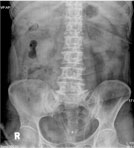

척추관 협착증의 방사선 소견